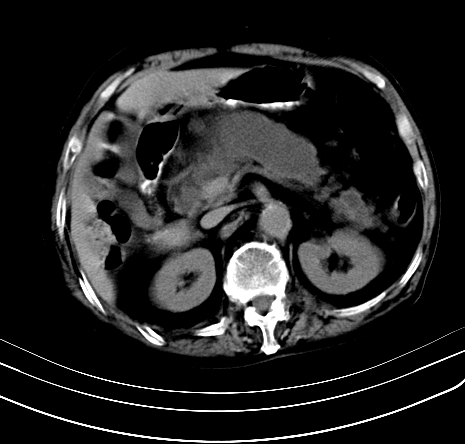

上腹部疼痛不适,行ct检查

胰腺明显肿大,密度减低,考虑慢性胰腺炎,假性囊肿形成不除外。

胰腺较明显扩大,胰周有渗出;肾周筋膜有增厚渗出,以左肾为著。应考虑急性胰腺炎。